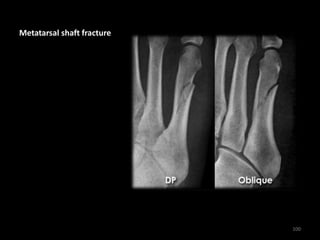

Metatarsal shaft fracture

100

• Oblique fracture of the

5th Metatarsal shaft

• Fracture more clearly

visible on the oblique

image

101